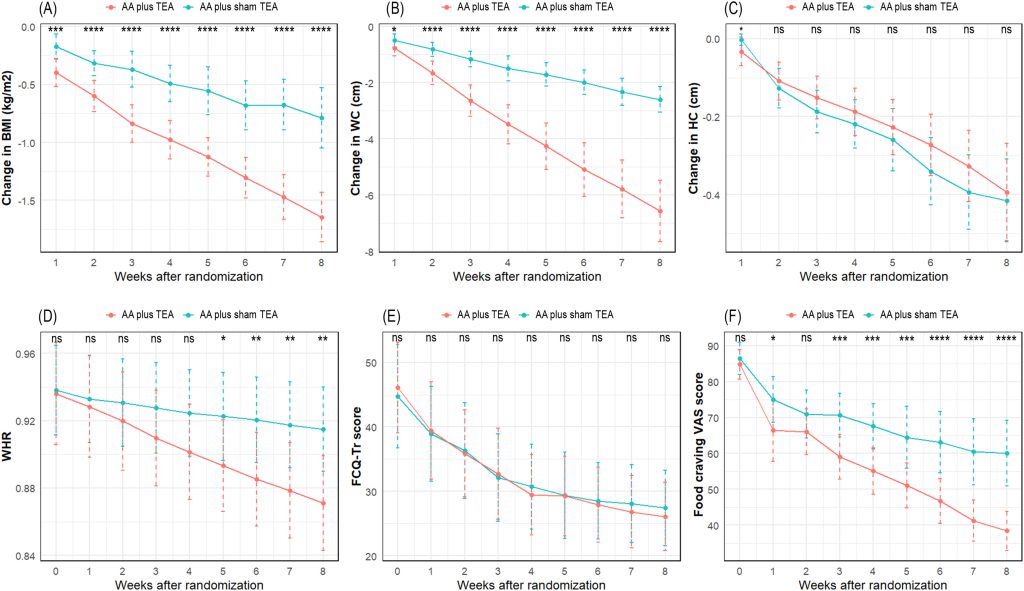

پس از هشت هفته، میانگین کاهش وزن بدن در گروه AA + TEA برابر با -4.45 (1.29) کیلوگرم و در گروه AA + TEA ساختگی برابر با -2.05 (1.33) کیلوگرم بود (MD [95 % CI]: 2.40 [1.75; 3.05]). کاهش BMI، WC، WHR و امتیاز VAS در گروه AA + TEA نسبت به گروه AA + TEA ساختگی به طور معناداری بیشتر بود. بین گروهها در مقیاس FCQ-Tr و HC تفاوت معناداری یافت نشد. هفت مورد عارضه جانبی ثبت شد که همگی خفیف بودند و بدون نیاز به درمان برطرف شدند.

**p < 0.0001 (مقایسه بین دو گروه با استفاده از آزمون تی دانشجویی). نقاط نشاندهنده میانگین و خطوط نشاندهنده انحراف معیار هستند.

شاخص توده بدنی (BMI) و دور کمر (WC) نیز کاهش مداوم را نشان دادند. اگرچه کاهش دور کمر در گروه AA + TEA پس از هشت هفته تفاوت معناداری با گروه AA + TEA ساختگی نداشت (ضمیمه ۳)، اما کاهش معنادار بیشتری در هر دو شاخص در گروه AA + TEA مشاهده شد (شکل ۲-A, B). پس از هشت هفته، تفاوت میانگین (MD) و فاصله اطمینان ۹۵٪ (CI) بین گروه AA + TEA و AA + TEA ساختگی برای BMI و WC به ترتیب ۰.۸۵ (۰.۶۱؛ ۱.۰۹) و ۳.۹۷ (۳.۱۴؛ ۴.۸۰) بود (جدول ۲).

- ns: تفاوت غیرمعنادار | * p < 0.05 | ** p < 0.01 | *** p < 0.001 | **** p < 0.0001 (مقایسه بین دو گروه با استفاده از آزمون تی دانشجویی)

- نقاط نشاندهنده میانگین و خطوط نشاندهنده انحراف معیار هستند.

- AA: طب سوزنی گوش | BMI: شاخص توده بدنی | FCQ-Tr: پرسشنامه ولع غذایی | HC: دور باسن | TEA: طب سوزنی کاشت نخ | VAS: مقیاس بصری ولع غذایی | WC: دور کمر | WHR: نسبت دور کمر به دور باسن

کاهش دور باسن (HC) در گروه AA + TEA پس از یک هفته از شروع مداخله کمی بهتر بود اما در مجموع، تغییرات قابلتوجهی در هر دو گروه مشاهده نشد (شکل ۲-C, جدول ۲). بنابراین، نسبت دور کمر به دور باسن (WHR) از هفته پنجم درمان در گروه AA + TEA کاهش معناداری نشان داد (MD [95% CI] = 0.04 [0.02; 0.07]) (شکل ۲-D, جدول ۲).

پرسشنامه ولع غذایی (FCQ-Tr) و مقیاس بصری ولع غذایی (VAS) در طول دوره مداخله در هر دو گروه کاهش یافت. با این حال، فقط مقیاس VAS در گروه AA + TEA کاهش معناداری بیشتری نسبت به گروه AA + TEA ساختگی داشت (MD [95% CI] = 21.6 [14.1; 29.2]) (شکل ۲-E, F, جدول ۲).